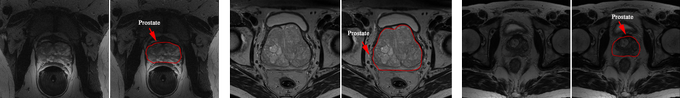

A weakly supervised registration-based framework for prostate segmentation via the combin... https://t.co/b8YQ9Bzt9U